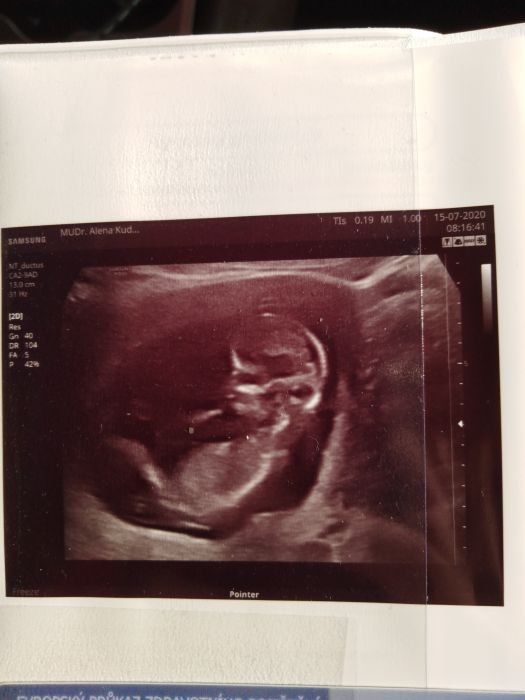

Přidávám fotku - mimčo se zrovna pohlo a cuca si palec

jo a mam uplne stejnou fotku ze screeningu jak od male z predloni

s prstikem v puse

Míšo-ello, krásná fotka. Termín vychází pěkný, ale ve finále je to jedno, kdy se mimčo narodí, hlavně, když se narodí a je zdravé